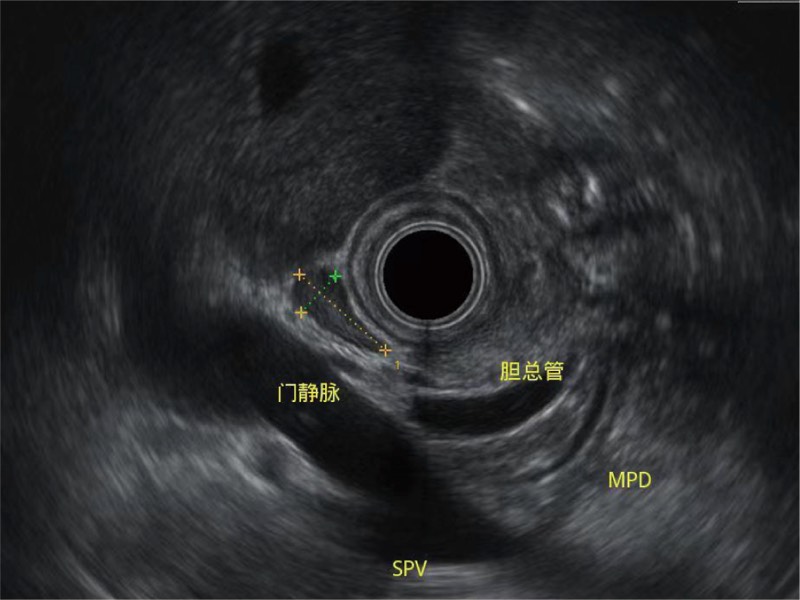

• 清晰显示胆总管及周围血管分布

• 匹配跟踪技术

随着组织深度的变化,超声接收频率进行智能匹配跟踪,确保图像中、远场良好的穿透力以及整场一致的分辨力,从而得到均一的画质